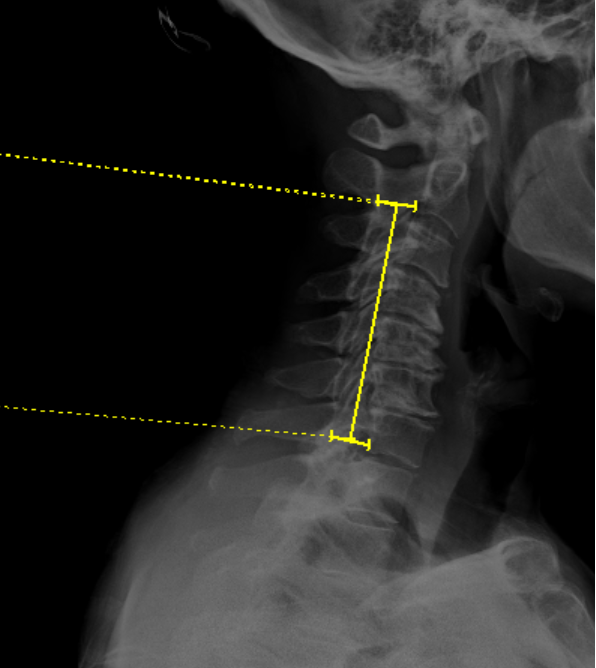

The K-Line is a line drawn between the midpoints of the anteroposterior (AP) diameter of the spinal canal at C2 and C7 on a neutral, standing lateral cervical spine X-ray. It was originally described by Fujiyoshi et al. (2008) as a single parameter that simultaneously evaluates both cervical sagittal alignment (kyphosis) and the size of ossification of the posterior longitudinal ligament (OPLL) to guide surgical decision-making.

·      Identify the midpoint of the anteroposterior (AP) diameter of the spinal canal at C2.

o   Measure the AP distance of the spinal canal at the C2 vertebral body level and mark the midpoint

·      Identify the midpoint of the AP diameter of the spinal canal at C7.

o   Similarly, measure and mark the midpoint of the spinal canal at C7

·      Draw a straight line connecting the two midpoints — this is the K-Line